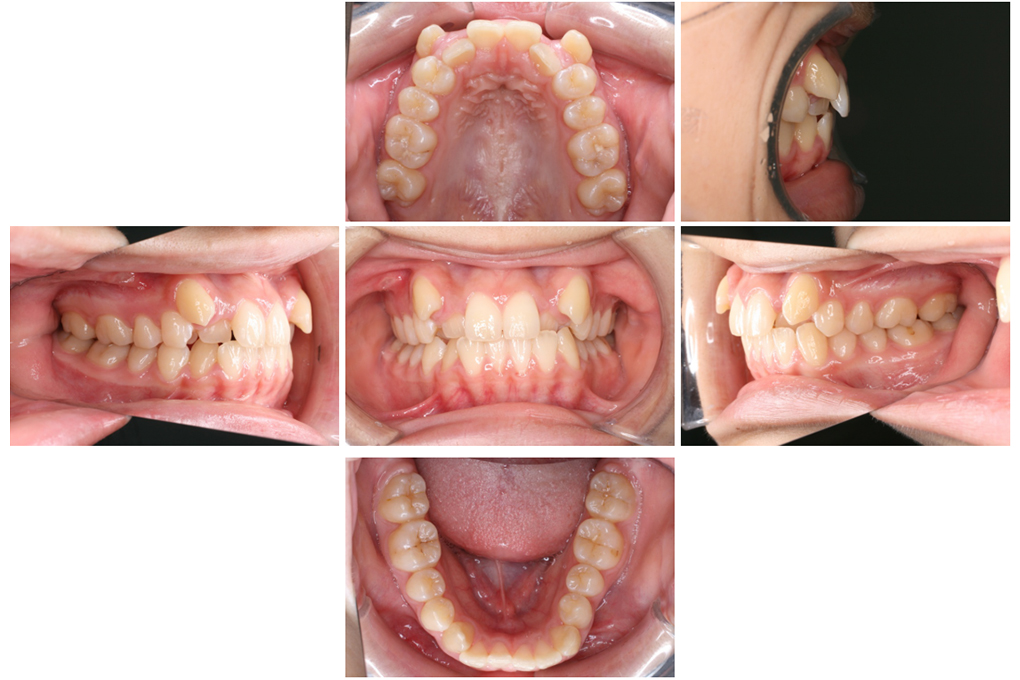

お口の中の写真撮影

お口の中の写真を撮影することで、歯の大きさや咬み合わせ、歯茎の状態などを確認することで、使用する装置、治療期間などが分かります。